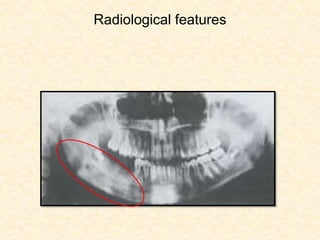

RADIOLOGICAL FEATURES

No early changes

Initial changes include blurring of the bony

trabeculae

Ill defined radiolucency

Moth eaten appearance